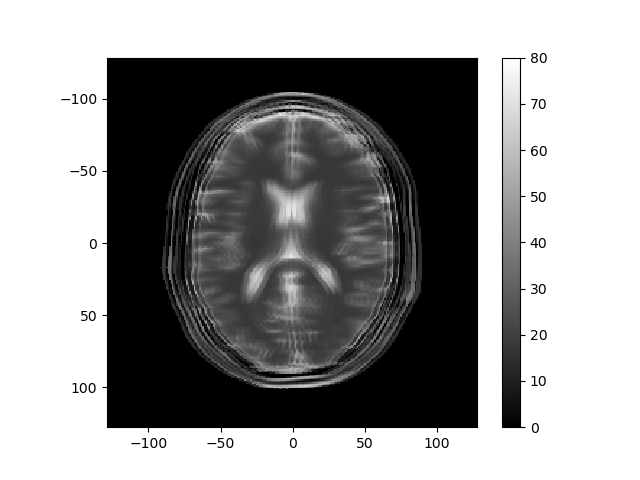

Consider how the image would change if the k-space data were multiplied by \sin^2(\cdot) or \cos^2(\cdot) of k_r or k_c. Below are several k-space representations that have been distorted in this way. In each case, assume that only the magnitude of the k-space data is changed. Match each k-space image with the corresponding reconstructed image, and enter your results from the corresponding pull-down list.

matching reconstructed image: